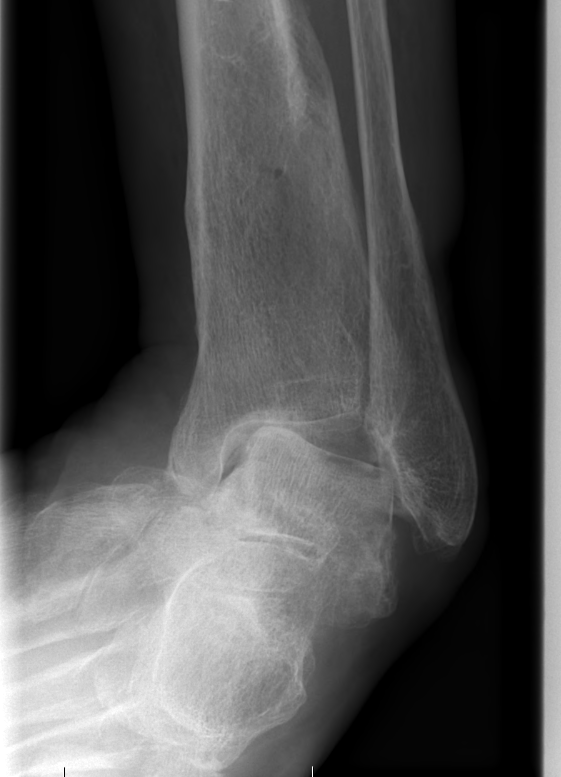

Combined ankle and subtalar joint osteoarthritis

Talar AVN

Trauma

Severe Deformity - acquired flat foot / neurological conditions / Charcot /

Ankle fracture in elderly patient with poor skin and co-morbities